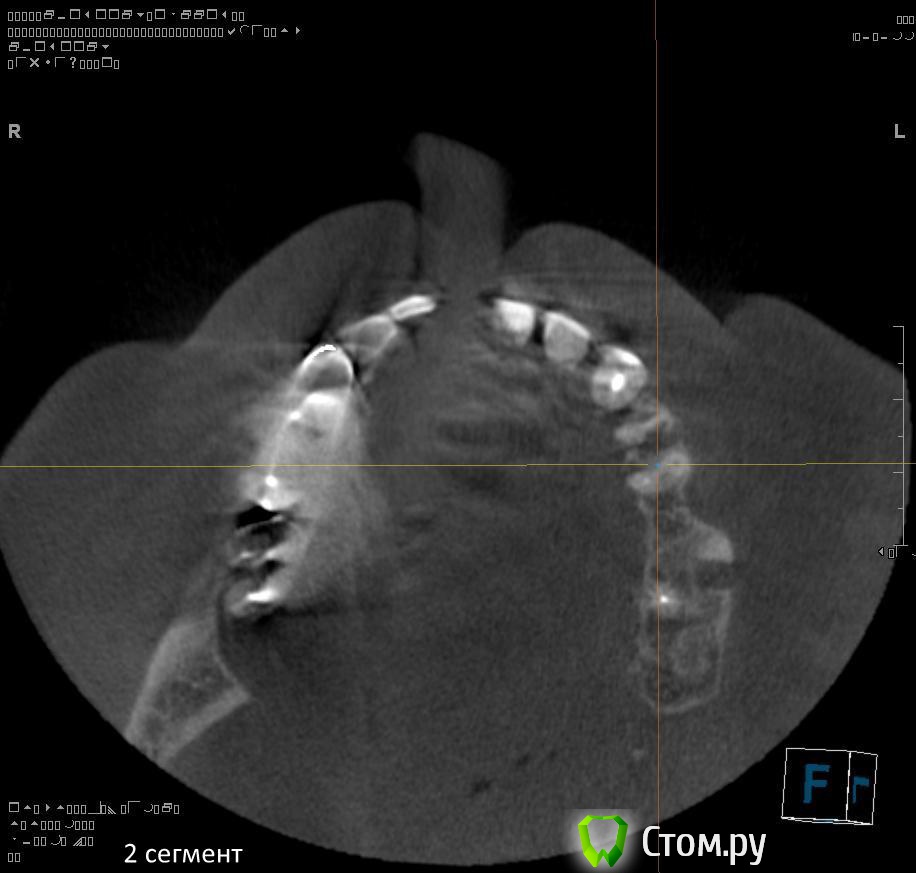

1. правильно ли я понимаю, что через 1,5 - 2 месяца после удаления 1.4 можно провести аугментацию (синус-лифтинг, латеральное окно, в первом сегменте, возможно с одномоментной установкой имплантатов)?

2. нужна ли в 1 сегменте дополнительная аугментация (по вертикали)?

7. через 2-3 месяца после удаления 2.4, 2.5, 2.6 провести открытый синуслифтинг во втором сегменте возможно с одномоментной установкой имплантатов?

1. Не правильно понимаете. Покажите ЛОРу на предмет хронического гайморита и инородных тел в пазухе.

2. Не нужна. Наростить много не получится.